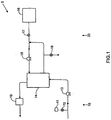

- Fig. 1 is a schematic representation of a hemodialysis system.

- the system 5 includes two flow paths, a blood flow path 10 and a dialysate flow path 20.

- Blood is drawn from a patient.

- a blood flow pump 13 causes the blood to flow around blood flow path 10, drawing the blood from the patient, causing the blood to pass through the dialyzer 14, and returning the blood to the patient.

- the blood may pass through other components, such as a filter and/or an air trap 19, before returning to the patient.

- anticoagulant may be supplied from an anticoagulant supply 11 via an anticoagulant valve 12.

- a dialysate pump 15 draws dialysate from a dialysate supply 16 and causes the dialysate to pass through the dialyzer 14, after which the dialysate can pass through a waste valve 18 and/or return to the dialysate feed via dialysate pump 15.

- a dialysate valve 17 controls the flow of dialysate from the dialysate supply 16.

- the dialyzer is a type of filter having a semi-permeable membrane, and is constructed such that the blood from the blood flow circuit flows through tiny tubes and the dialysate solution circulates around the outside of the tubes. Therapy is achieved by the passing of waste molecules (e.g., urea, creatinine, etc.) and water from the blood through the walls of the tubes and into the dialysate solution. At the end of treatment, the dialysate solution is discarded.